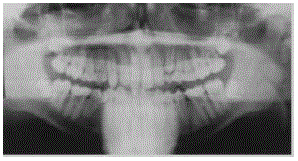

Com relação aos achados radiográficos presentes na situação clínica ilustrada na figura acima, assinale a opção correta.